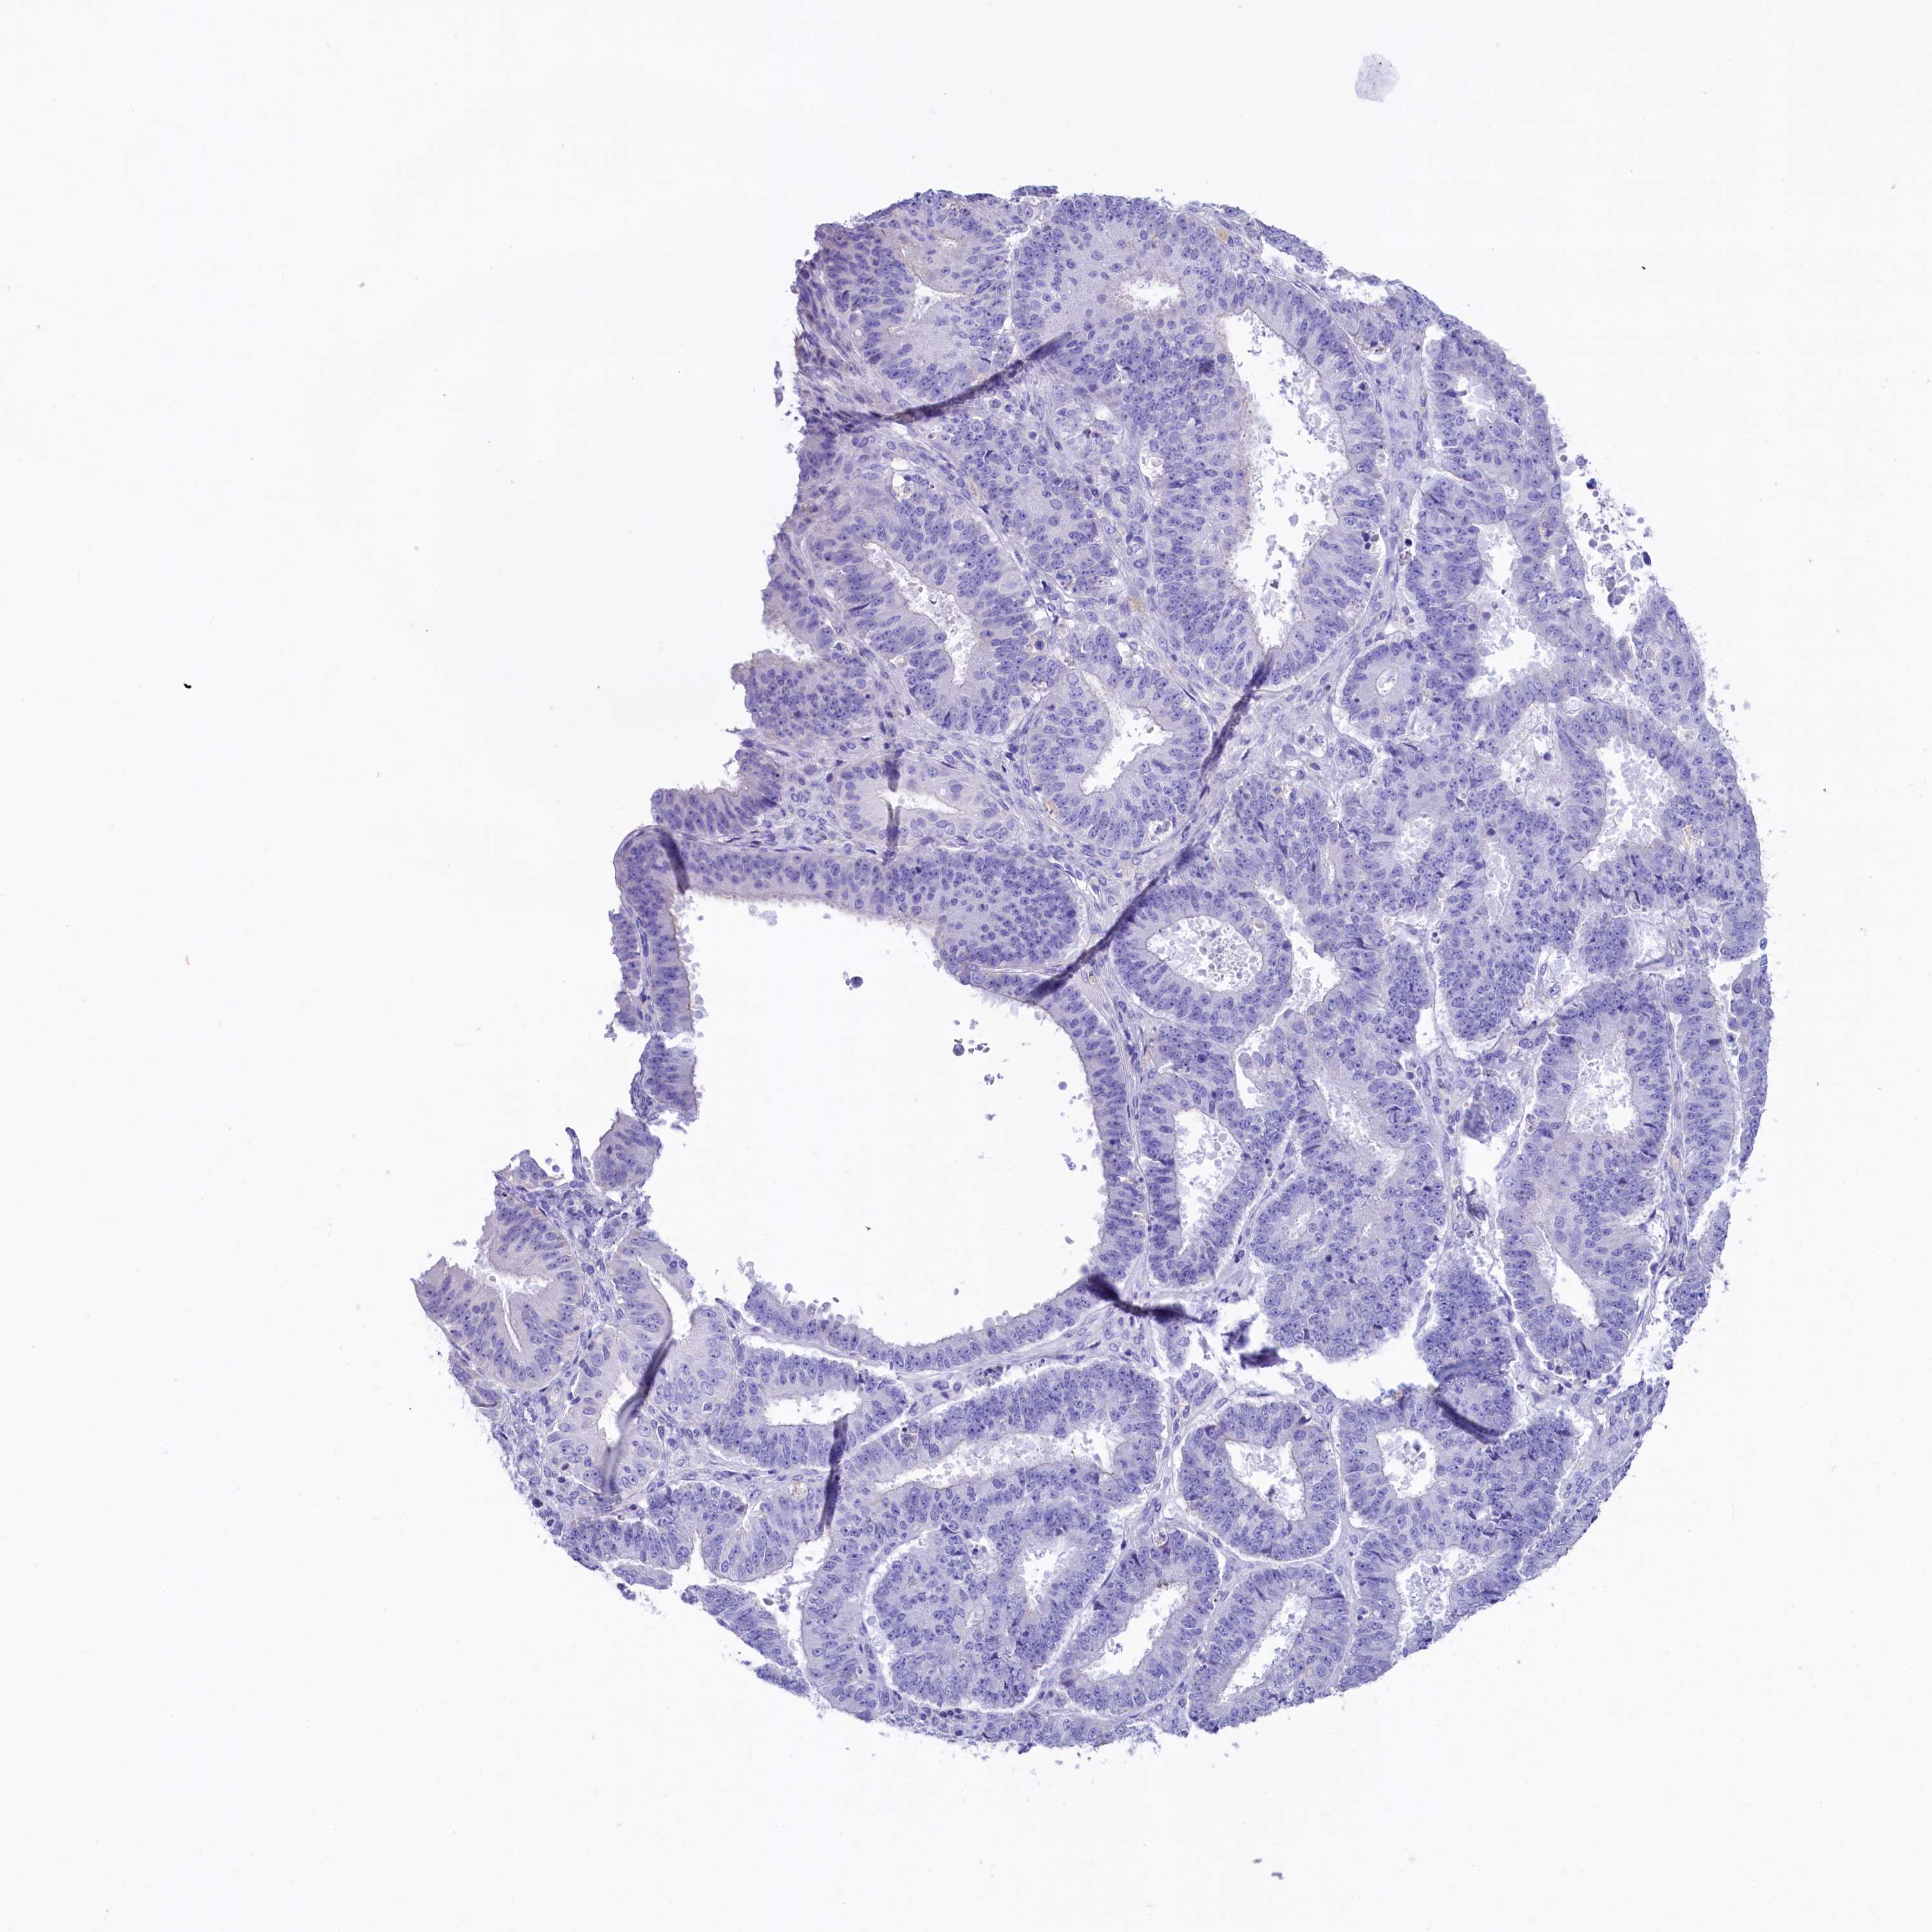

OVARIAN CANCER - Protein expressioni

A mouse-over function shows sample information and annotation data. Click on an image to view it in a full screen mode. Samples can be filtered based on level of antibody staining by selecting one or several of the following categories: high, medium, low and not detected. The assay and annotation is described here.

Note that samples used for immunohistochemistry by the Human Protein Atlas do not correspond to samples in the TCGA dataset.

Antibody stainingi

Antibody staining in the annotated cell types in the current human tissue is reported as not detected, low, medium, or high, based on conventional immunohistochemistry profiling in selected tissues. This score is based on the combination of the staining intensity and fraction of stained cells.

Each image is clickable and will lead to virtual microscopy that enables deeper exploration of all samples and also displays staining intensity scores, fraction scores and subcellular localization as well as patient and tissue information for each sample.

Antibody HPA041301

Antibody HPA044239

Staining

High

Medium

Low

Not detected

Intensity

Strong

Moderate

Weak

Negative

Quantity

>75%

75%-25%

<25%

None

Location

Nuclear

Cytoplasmic/membranous

Cytoplasmic/membranous,nuclear

Cystadenocarcinoma, serous, NOS

Carcinoma, endometroid

Cystadenocarcinoma, mucinous, NOS

Carcinoma, NOS